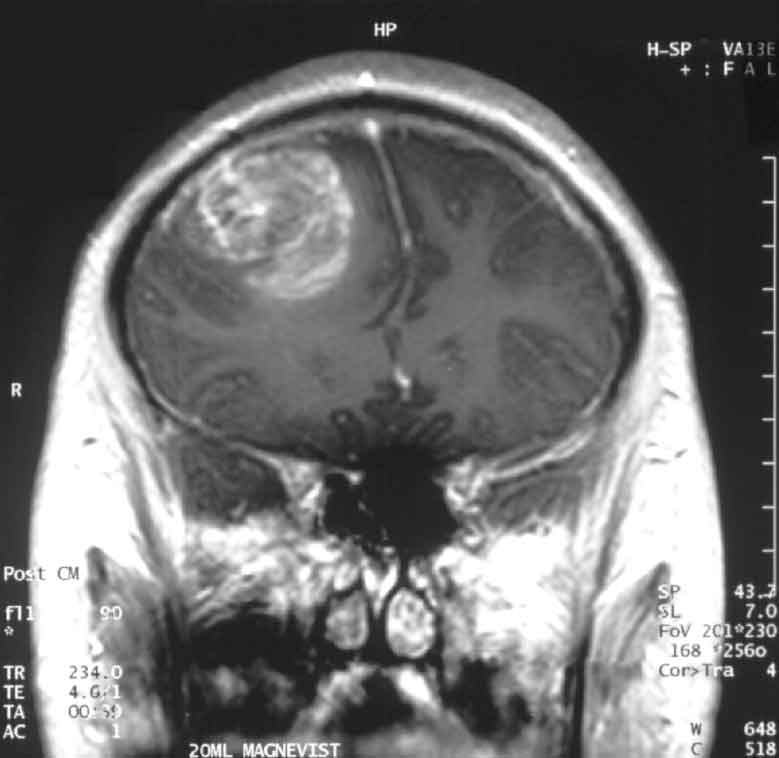

Злокачественные опухоли мозга, как правило, представляют собой метастазы злокачественных новообразований, развивающихся в другой части тела. Рак молочной железы и легких, злокачественная меланома и злокачественные заболевания крови, например лейкоз и лимфома, способны распространяться по кровеносному руслу и проникать в головной мозг. Метастазы могут возникать в одной или нескольких областях головного мозга. Первичные опухоли мозга растут из клеток самого головного мозга. Обычно это глиомы, образующиеся из глиальных клеток, которые окружают и поддерживают нейроны. Некоторые глиомы являются злокачественными, например наиболее распространенная из них мультиформная глиобластома. К другим злокачественным глиомам относятся быстро растущие анапластические астроцитомы, медленнее растущие астроцитомы и олигодендроглиомы. Довольно редкие медуллобластомы отмечаются у детей в период, предшествующий половому созреванию. Саркомы и аденокарциномы, образующиеся не из нервной ткани, встречаются нечасто. Опухоли мозга возникают с равной частотой независимо от половой принадлежности, но некоторые их виды более распространены у мужчин, а другие - у женщин. По неизвестным причинам в последнее время стали чаще появляться лимфомы головного мозга, особенно у больных СПИДом. Несмотря на лечение, только около 25% людей со злокачественными опухолями мозга живут больше двух лет. При определенных типах опухолей перспектива немного лучше, например при астроцитомах и олигодендроглиомах опухоль обычно не возобновляет своего роста в течение 3-5 лет после лечения. Около 50% людей, лечившихся по поводу медуллобластомы, живут более 5 лет после установления диагноза. Лечение злокачественной опухоли мозга имеет лучшие перспективы при анапластической астроцитоме, чем при мультиформной глиобластоме, а также если возраст больного не превышает 45 лет и если большая часть опухоли или вся она может быть удалена хирургически.